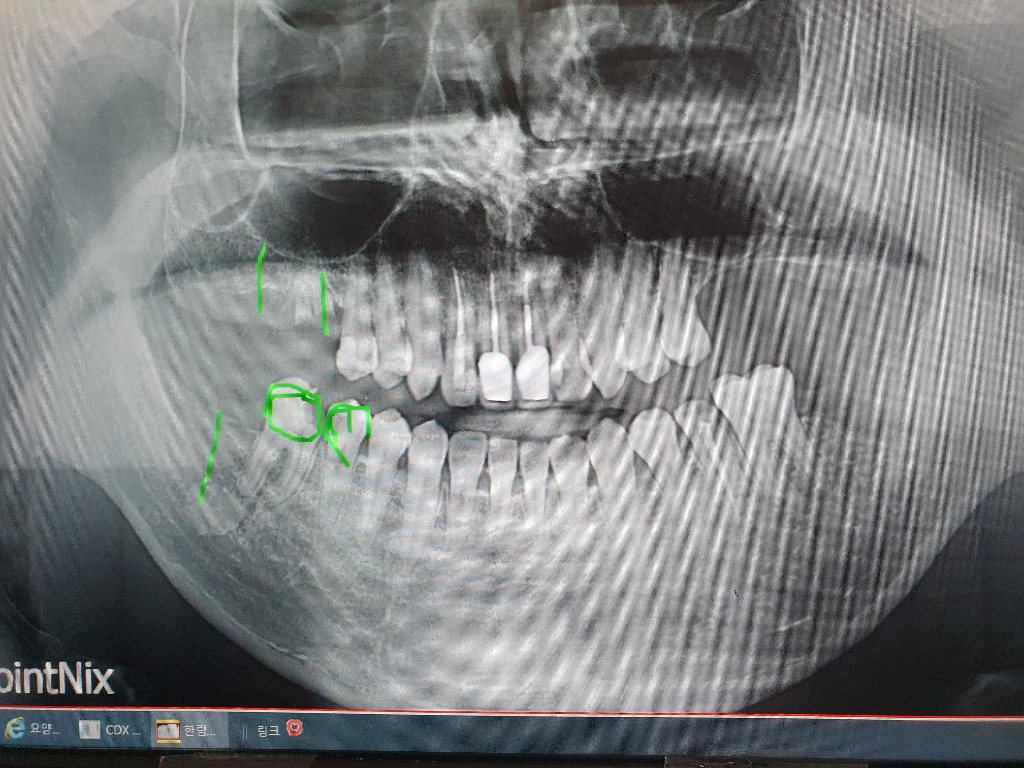

위 사진은 1달전 사진입니다 우측의 위에 발치한지 5년도 넘어서 뼈가 많이 얇아졌는데 저렇게 계속 두면 무슨일이 생기는지 심각성을 좀 알려주세요